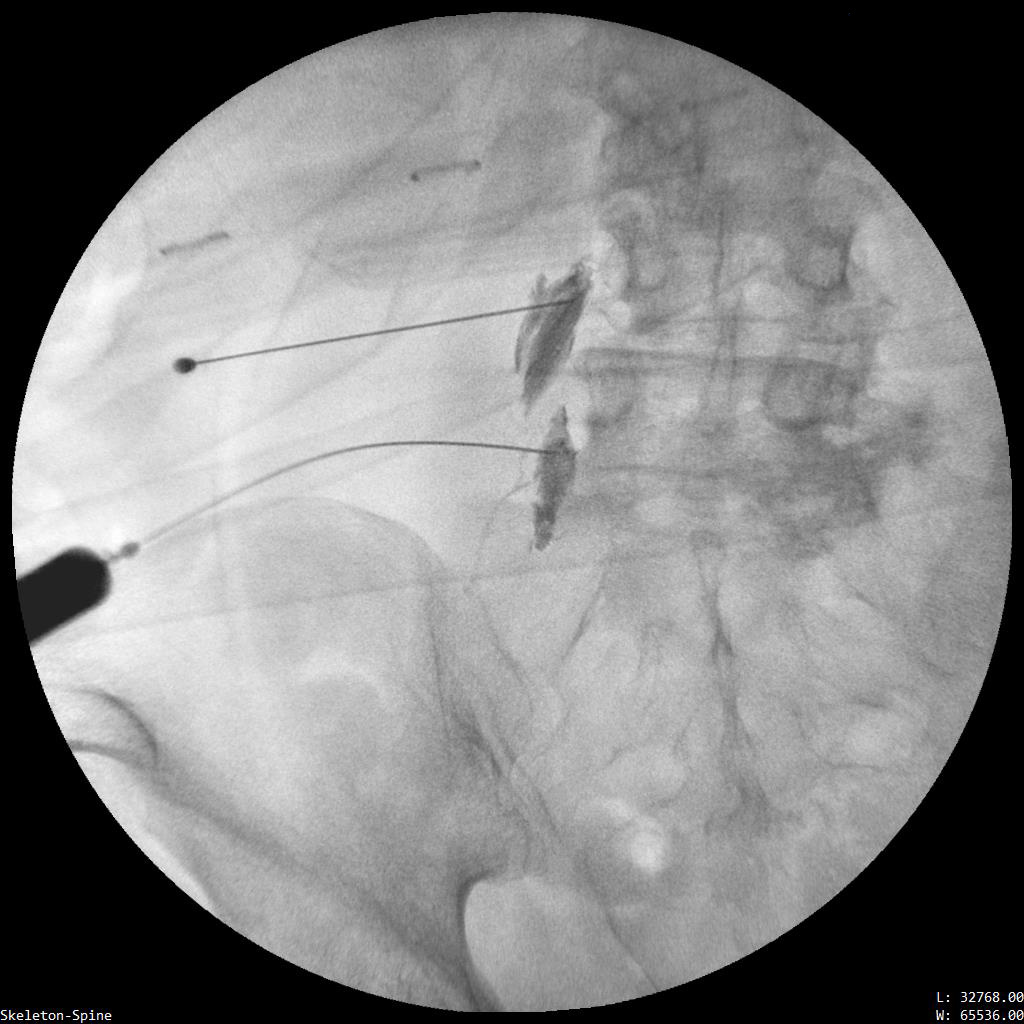

Ασθενής με 2 πολύ μεγάλες δισκοκήλες

Ασθενής 75 ετών με αδυναμία βάδισης λόγω έντονης οσφυαλγίας από έτους. Η αιτία είναι δύο μεγάλες δισκοκήλες που πιέζουν τις εξερχόμενες ρίζες των νεύρων. Με τοπική αναισθησία τοποθετήθηκαν 2 βελόνες στα στα  επίπεδα Ο4-05 και Ο5-Ι1 και έγινε  εισαγωγή μείγματος αναλγητικών. Άμεση ανακούφιση με αποτέλεσμα που διατηρείται 1 χρονο μετά.